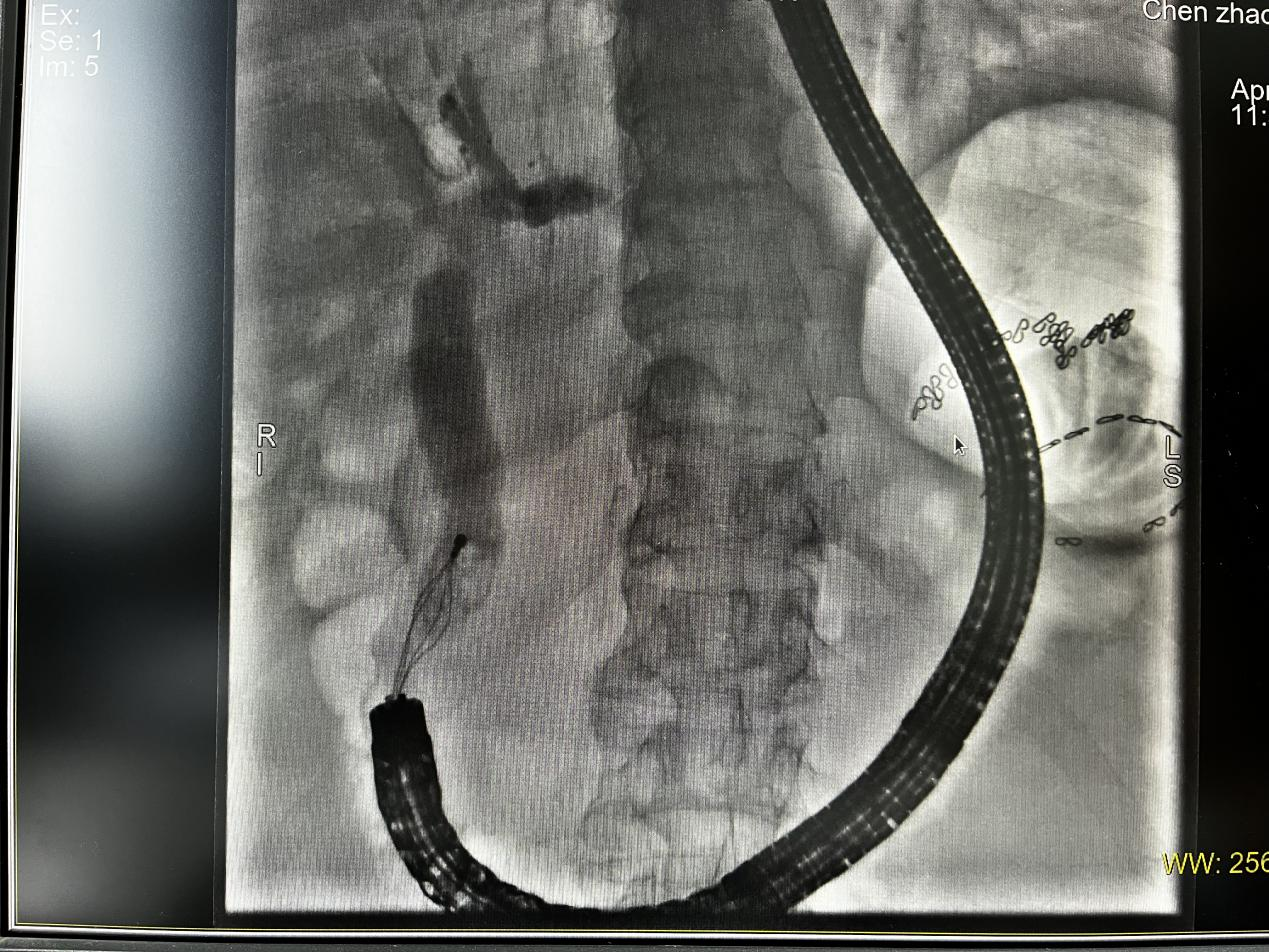

X线下网篮取石

术中,消化内科团队凭借丰富的经验,在肠镜引导下巧妙调整进镜角度,成功定位乳头并完成插管,最终顺利取出胆总管结石。手术全程患者生命体征平稳,未出现出血、穿孔等并发症。患者住院6天,症状完全缓解,目前已康复出院。